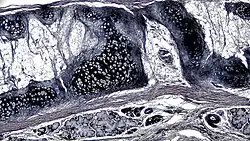

![]() A cross section of mammalian elastic cartilage | |

Elastic cartilage, fibroelastic cartilage or yellow fibrocartilage [1] is a type of cartilage present in the pinnae (auricles) of the ear giving it shape,[2] provides shape for the lateral region of the external auditory meatus,[3] medial part of the auditory canal[3] Eustachian tube, corniculate and cuneiform laryneal cartilages,[3] and the epiglottis. It contains elastic fiber networks and collagen type II fibers.[4] The principal protein is elastin.

Elastic cartilage is histologically similar to hyaline cartilage but contains many yellow elastic fibers lying in a solid matrix. These fibers form bundles that appear dark under a microscope. The elastic fibers require special staining since when it is stained using haematoxylin and eosin (H&E) stain it appears the same as hyaline cartilage.[3] Verhoeff van Geison stains are used (giving the elastic fibers a black color), but aldehyde fuchsin stains, Weigert's elastic stains, and orcein stains also work.[3] These fibers give elastic cartilage great flexibility so that it is able to withstand repeated bending. Similarly to hyaline one or multiple chondrocytes lie between the spaces (or lacunea) in the fibres.[2] The chondrocytes only make up 2% of the tissue's volume.[2] Chondrocytes and the extracellular matrix are contained in an outerlayer named the perichondrium[2] (which is a layer of dense irregular connective tissue that surrounds cartilage which is independent of the joint).[3] It is found in the epiglottis (part of the larynx), and the pinnae (the external ear flaps of many mammals). Elastin fibers stain dark purple/black with Verhoeff's stain.

The extracellular matrix contains Elastin, fibrillin, glycoproteins, collagen types II, IX, X, and XI, and the proteoglycan aggrecan.[2] the components within the extracellular matrix are produced by the chondroblasts located within the edges of the perichondrium.[2]